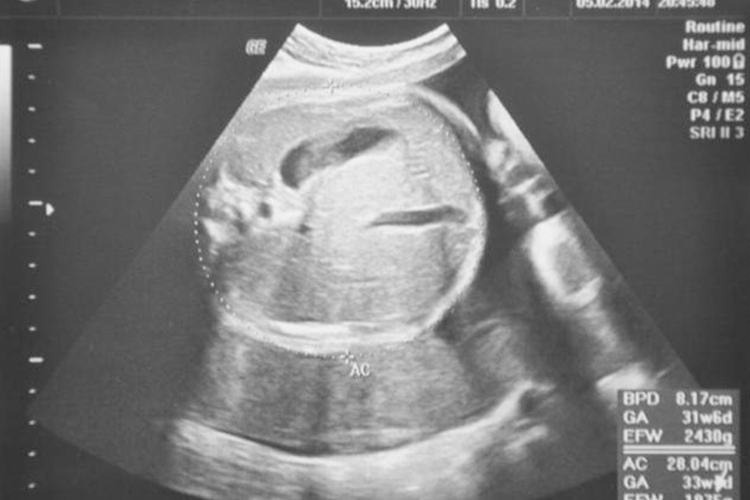

胎儿BPD、HC、AC、FL、HL是孕期进行B超检查时常见的指标,分别代表不同的生长参数,用于评估胎儿的生长发育情况。

1、BPD(双顶径):指胎儿头部左右两侧最宽部位之间的长度,即胎儿头部两侧顶骨最宽部位的直径测量的长度。在怀孕的不同时期,胎儿双顶径会有所变化。通过双顶径可以判断胎儿的发育情况,也可以推算怀孕的大概时间以及胎儿的体重。当胎儿双顶径>8.5cm时,通常认为胎儿已经基本发育成熟。

3、AC(腹围):指胎儿腹部一周的长度。腹围在一定程度上可以反映胎儿的大小。通过腹围的测量,医生可以评估胎儿的体重和发育状况。